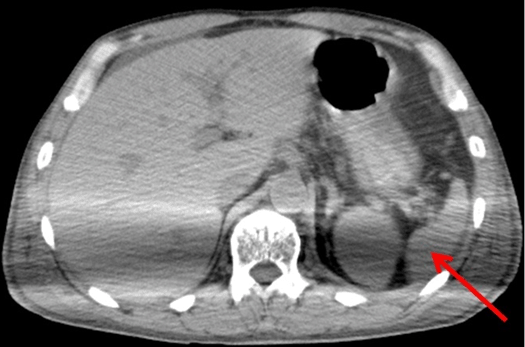

A 57-year-old previously healthy male presented to the emergency department with a three-day history of generalized malaise, muscle ache, and fever. His vital signs and physical examination results were normal. Blood tests showed no abnormalities except leukocytosis. He was discharged with a presumptive diagnosis of common cold. However, the next day, he was brought to the emergency department after experiencing a syncopal episode. Vital signs on admission were as follow: temperature 38.7°C (101.7°F), blood pressure 73/47 mmHg, pulse rate of 132 beats per min, respiratory rate of 24 breaths per min, and arterial oxygen saturation level of 96% while breathing ambient air. He was alert and oriented. There was no nuchal rigidity. Mottled skin was noted on the arms, chest, abdomen, and pretibial areas. Findings from lung, heart, and abdomen examinations were normal. Initial laboratory tests revealed thrombocytopenia 43×109/L, a normal white blood cell count (7.2×109/L), and a normal hemoglobin level (13.6 g/dL). Coagulation studies showed findings consistent with DIC, namely a prothrombin time of 12.3 s, partial thromboplastin time of 53.5 s, fibrin degradation product concentration of 69.7 µg/mL, and D-dimer concentration of 21.4 mg/mL. Liver and renal function tests revealed an aspartate aminotransferase level 150 U/L, alanine aminotransferase level 35 U/L, total bilirubin level 1.58 mg/dL, blood urea nitrogen level 40.7 mg/dL, and creatinine level 3.09 mg/dL, which were indicative of the multiple organ dysfunction syndrome. The serum troponin I level was normal on admission, but was elevated to 6.35 ng/mL within several hours. Arterial blood gas analysis detected an anion gap metabolic acidosis with an elevated lactic acid level of 33.80 mg/dL. Serological test results for HIV, hepatitis B virus, hepatitis C virus, and syphilis were negative. Chest radiography showed no pathological findings, however, computed tomography of the abdomen revealed a small spleen, 61 cm3 in size (Figure 1). Erythrocyte inclusions (Howell–Jolly bodies) were observed on the peripheral blood smear (Figure 2). An electrocardiogram demonstrated sinus tachycardia with no ST-T changes. Echocardiography showed diffuse hypokinesis with an ejection fraction of 18% without vegetation, or valvular disease. Based on the patient’s fever and shock state, as well as his poor cardiac function and elevated troponin, septic shock and cardiogenic shock were considered in the differential diagnosis. Fluid resuscitation and norepinephrine were administered immediately, followed by endotracheal intubation and mechanical ventilation. Therapy with vancomycin and meropenem was empirically initiated after blood cultures were obtained. Cardiac catheterization confirmed the absence of any critical coronary artery disease. Myocardial biopsy revealed normal findings on microscopy. Intra-aortic balloon pumping was begun for possible cardiogenic shock. Renal failure was managed with continuous renal replacement therapy. Nine hours after admission, blood culture showed the growth for gram-positive cocci and the antibiotic regimen was changed to vancomycin and ceftriaxone. Initial resuscitative management resulted in a reduction of the serum lactate levels and hemodynamic stabilization. Norepinephrine was subsequently discontinued. Intra-aortic balloon pumping was stopped after 48 hours, and continuous renal replacement therapy was replaced with intermittent hemodialysis. Two days after admission, S. pneumoniae, was identified in blood culture, and a diagnosis of invasive pneumococcal disease was made. The patient was weaned off the ventilator on day-7. The patient developed painful ischemic lesions on both his hands and feet during the week after admission, which gradually spread to his forearms and lower legs (Figure 3A–B). By day-5, the peripheral arteries, including the bilateral radial, dorsalis pedis, and posterior tibial arteries, were not palpable. Portions of the skin lesions became vesiculated and edematous, producing hemorrhagic bullae. Gradually, the lesions became more consolidated with dark-colored well-demarcated hemorrhagic necrosis (Figure 3C–D). These findings were consistent with purpura fulminans, due to S. pneumoniae,. Seven weeks after admission, below-elbow amputations and below-knee amputations were performed bilaterally. After a four-month hospital stay, the patient was transferred to another hospital for further rehabilitation. | ||||||

Purpura fulminans was first reported by Guelliot in 1884 [7] , and is a life-threatening condition characterized by symmetric peripheral gangrene with large purpuric skin lesions, fever, hypotension, and DIC that requires early diagnosis and treatment. Various pathophysiological mechanisms contribute to the formation of the necrotizing inflammatory lesions, and purpura fulminans carries a risk of hypotension and death in up to 40% of cases [1]. The most common causative agents of purpura fulminans are N. meningitides infections, followed by varicella, S. pneumoniae, and measles infections [8]. Reduced splenic function, asplenism, and protein S, or C deficiency can also be risk factors for this condition [2][4][5]. The skin lesions usually start as well-demarcated erythematous macules, which worsen rapidly with hemorrhagic necrosis, followed by the formation of dark lesions with vesicles or bullae. The differential diagnosis of purpura fulminans includes idiopathic thrombocytopenic purpura, thrombotic thrombocytopenic purpura, Henoch–Schönlein purpura, and warfarin-induced skin necrosis [9]. Usually, only purpura fulminans and warfarin-induced skin necrosis present with necrotic skin lesions [5]. Currently, there is no standard treatment for purpura fulminans caused by sepsis, and intensive care is the main therapeutic strategy. In addition to aggressive fluid resuscitation, prompt initiation of empirical broad-spectrum antibiotics for underlying sepsis, correction of acid-base imbalance and electrolyte abnormalities, and the early administration of oxygen are also helpful [10][11]. Heparin may be administered to inhibit further thrombus formation, and may reverse the development of skin necrosis [12], Because the pathophysiology of purpura fulminans involves intravascular thrombosis. Fresh frozen plasma can be used to replete these coagulation factors. Replacement therapy may contribute to arresting the progression of the disease and avoiding amputation of the limbs [5]. Early administration of protein C corrects the deficiency and might contribute to the restoration of peripheral perfusion according to a previous case report [5]. As in our case, the first manifestation of purpura fulminans may be a non-specific flu-like illness, with fever or chills, sore throat, malaise, and occasionally gastroenteritis symptoms, which occur 12–24 hours before the development of purpura fulminans [13][14]. Therefore, clinicians should be cognizant of purpura fulminans as a differential diagnosis in patients in a shock state, with non-specific flu-like symptoms, and consider empirical antibiotic treatment, even in patients who initially lack the characteristic skin manifestations associated with purpura fulminans. Patients with asplenism and reduced splenic function are particularly at a risk of sepsis. Functional asplenia or hyposplenia can result from splenectomy or various splenic conditions, such as congenital absence, atrophy following repeated infarction (e.g., sickle cell disease), gastrointestinal diseases, hepatic disorders, autoimmune disorders, hematological disorders, and neoplastic disorders [15]. Although scintigraphic methods are most reliable for assessing splenic function, they are not the best options for screening large populations [16]. The presence of Howell-Jolly bodies, which are small round bodies representing nuclear remnants within erythrocytes, indicates splenic dysfunction, although these findings may not be seen in those with only mild impairment of splenic function [5][16]. Other abnormalities associated with splenic dysfunction that can be seen on peripheral blood smears are acanthocytes (spur cells), target cells, hemoglobin remnants (Heinz bodies), siderocytes, and iron granulocytes [16]. In our case, Howell–Jolly bodies were observed on peripheral blood smear. The mean splenic length and width in healthy populations are 10.8 cm, and 3.6 cm, respectively [17], and the average volume is 131 cm3 [18]. Our patient’s splenic volume was 61 cm3 (6.2 cm long and 3.3 cm wide), which is small according to previous studies. Although there have been no studies on the association between splenic hypoplasia and dysfunction, there have been case reports of purpura fulminans due to S. pneumoniae associated with splenic hypoplasia [19][20][21]. It is rare for immunocompetent adults to have purpura fulminans, and only two such cases have been reported in literature [6]. Although our patient was relatively healthy until diagnosis, he was found to have a degree of splenic dysfunction, possibly due to splenic hypoplasia. The Centers for Disease Control and Prevention recommends the administration of pneumococcal vaccines for asplenic patients; this vaccine protects patients against 73–90% of strains causing post-splenectomy infections [22]. Other guidelines also recommend that patients with asplenia or hyposplenia be immunized against organisms including S. pneumoniae, H. influenzae type b, and N. meningitidis [22][23]. When a person is incidentally found to have splenic hypoplasia, vaccination against S. pneumoniae to prevent the devastating disease of purpura fulminans may need to be considered. With deep and extensive skin damage, surgical intervention including fasciotomy, debridement, and limb amputation are possible options. Some reports [8][24] suggest that prompt surgical consultation for the indications of intervention, debridement, and amputation may reduce the risk of mortality because critical complications, including the compartment syndrome, can occur in up to 7% of purpura fulminans cases, leading to increased morbidity [25]. Conversely, Johansen et al. do not recommend early surgical intervention because the damaged skin area is eventually localized [11]. In our case, it was difficult to determine the extent of necrosis at an early stage because the skin lesion margins were indistinct. After the patient’s general condition stabilized, the margins became apparent. Additional studies are needed to evaluate whether early surgical intervention is necessary to save the patient’s life, or if it is better to wait for a clearer demarcation of the necrotic areas. | ||||||